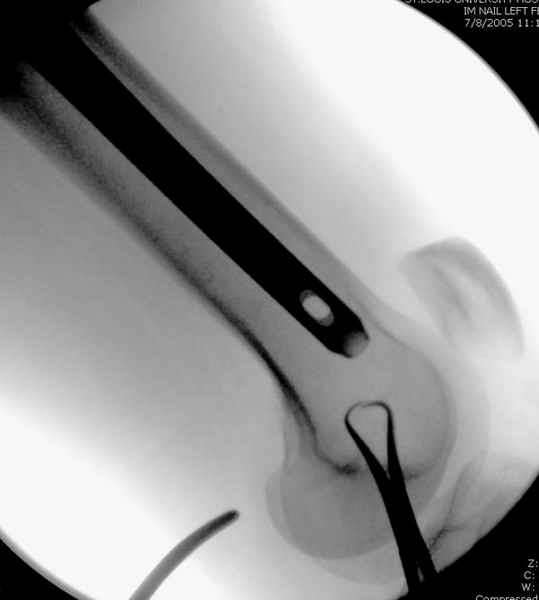

Как раз недавно у меня был примерный случай: больному 36 лет, поступил ночью, травма в результате мотоциклетной аварии, кроме чрезвертельного и спирального перелома левого бедра имеется переломы костей предплечья с этой же стороны. Скелетное вытяжение, а на следующий день больной про оперирован на ортопедическом столе с дистракцией. Чтобы не расколоть чрезвертельный перелом провели временную спицу ближе к переднему кортексу, из малого разреза костодержатель для репозиции, а фиксацию провели антиградным штифтом. Этапы операции на снимках.

Больной долго оставался нестабильным, только на 14 день удалось заменить на антеградный интромедуллярный штифт TFN (trochanteric femoral nail) SmithNephew. После неудачной попытки закрытой репозиции, несмотря на использование "joystick", проксимальный стержень от

наружного фиксатора, (перелом начал срастаться) репозицию провели из малого доступа, затем остальные этапы операции.